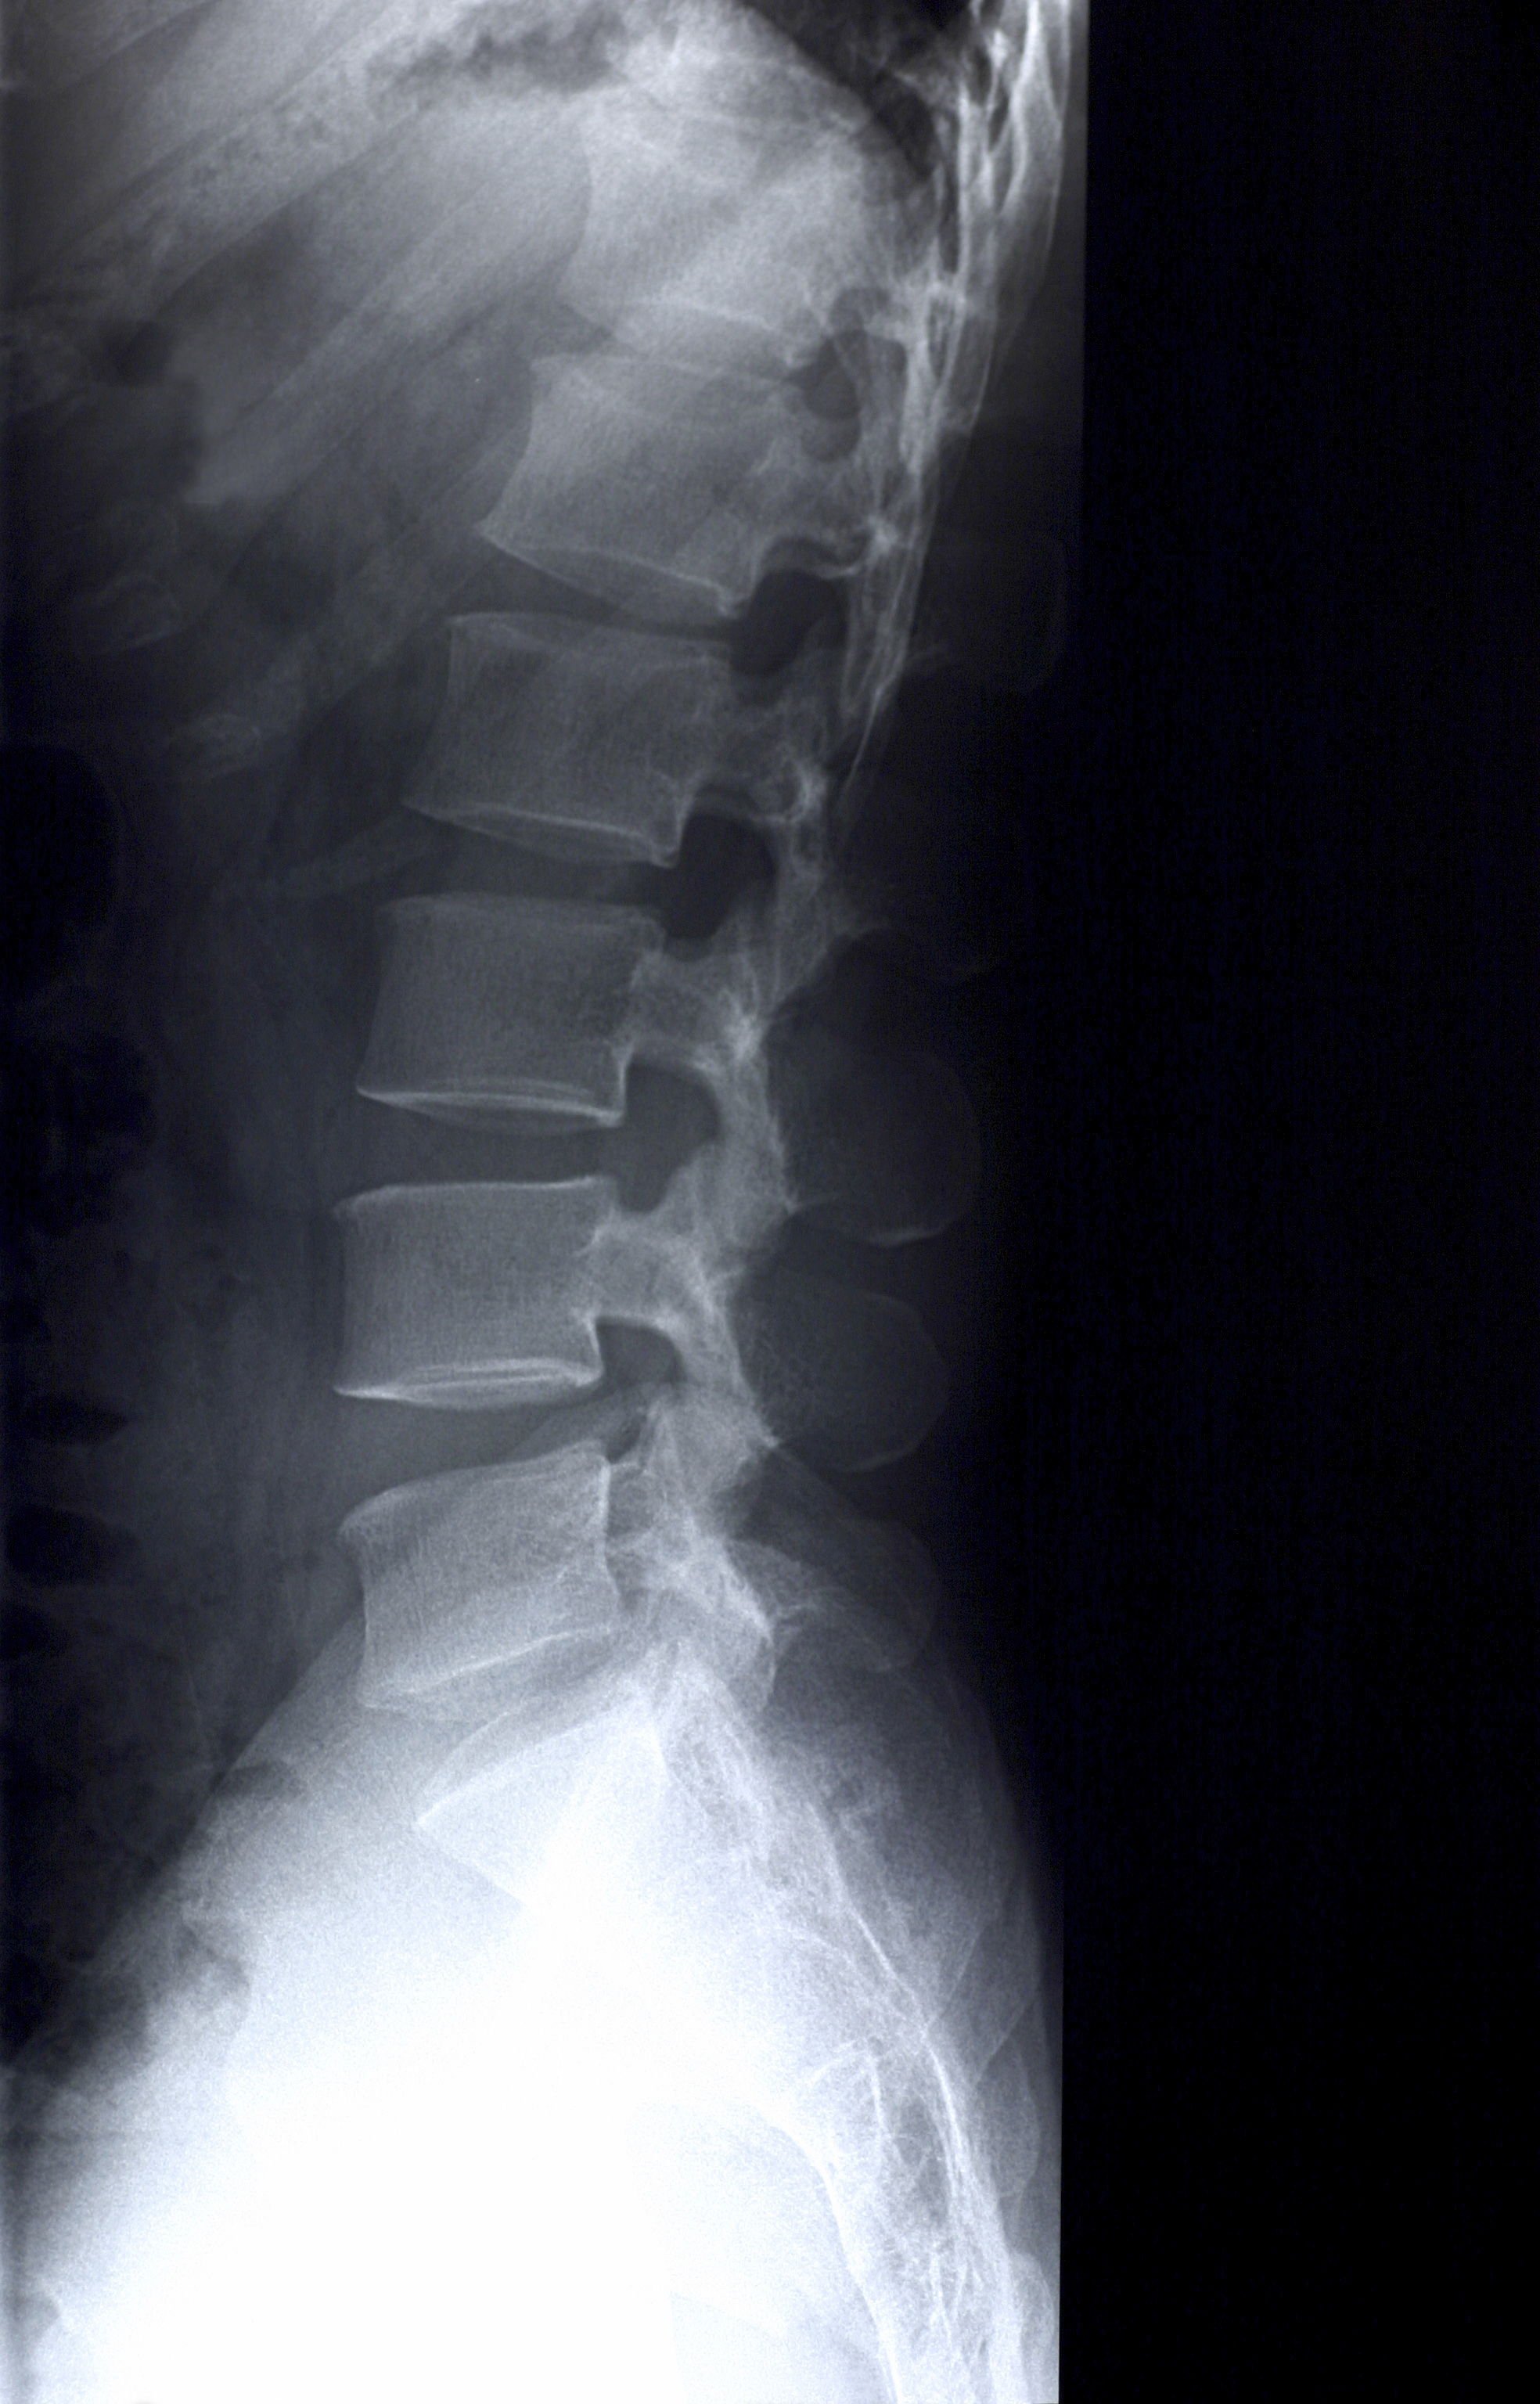

Arthritis of the back, Xray Stock Image M110/0498 Science Photo

Lumbar spine xray of a 79 year old woman with degenerative arthritis What Does Arthritis In The Lower Back Look Like On An X Ray Osteoarthritis (noninflammatory or degenerative arthritis) is the most common form of spinal arthritis. Lumbar arthritis affects the lumbar portion of the spine, or lower back, which is situated just above the pelvis. The disks can protrude or herniate and pinch a nerve or produce pressure on. It usually affects the lower back and. Paula moore posture doctor demonstrates spinal arthritis.. What Does Arthritis In The Lower Back Look Like On An X Ray.

Osteoarthritis of the lumber spine, Xray Stock Image C036/8214 What Does Arthritis In The Lower Back Look Like On An X Ray Osteoarthritis (noninflammatory or degenerative arthritis) is the most common form of spinal arthritis. Lumbar arthritis affects the lumbar portion of the spine, or lower back, which is situated just above the pelvis. The lower back is the most. Osteoarthritis of the spine is a breakdown of the cartilage of the joints and discs in the neck and lower back. The. What Does Arthritis In The Lower Back Look Like On An X Ray.

XRay Image Of Lumbosacral Spine Showing Osteoarthritis Of Lumbar What Does Arthritis In The Lower Back Look Like On An X Ray The lower back is the most. It usually affects the lower back and. Paula moore posture doctor demonstrates spinal arthritis. Lumbar arthritis affects the lumbar portion of the spine, or lower back, which is situated just above the pelvis. Osteoarthritis of the spine is a breakdown of the cartilage of the joints and discs in the neck and lower back.. What Does Arthritis In The Lower Back Look Like On An X Ray.